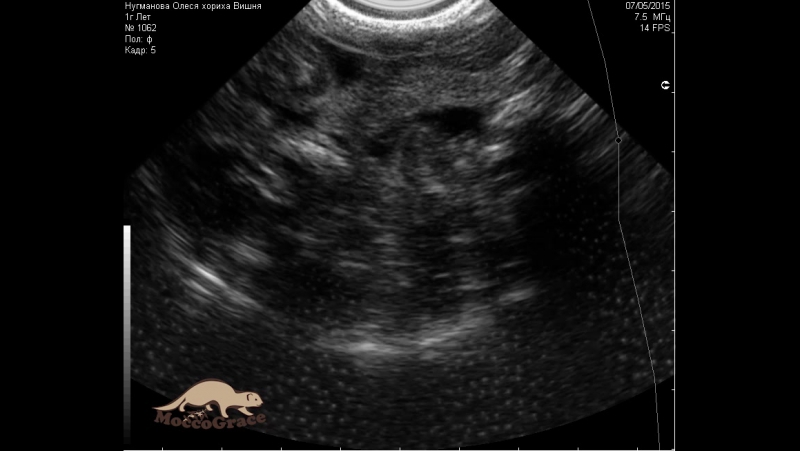

Узи терновка

Узи терновка 112 фото